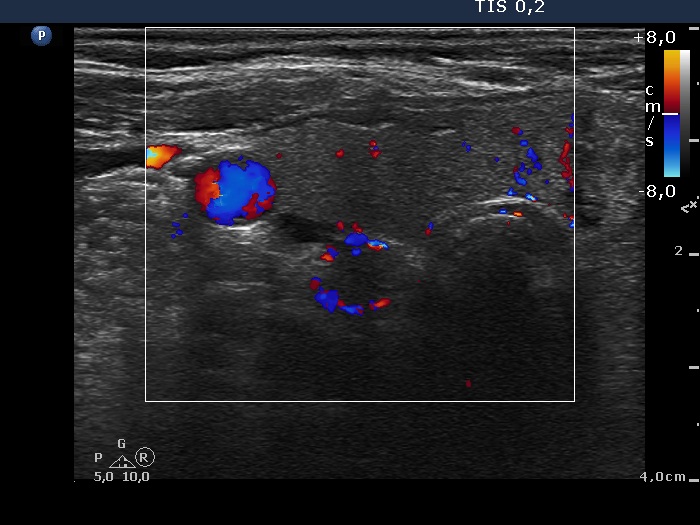

Ultrasonography. The thyroid was echonormal and had a small hypoechogenic lesion in the ventrolateral part of the right lobe. There was a hyperechogenic nodule having coarse calcification in the isthmus while the left lobe also had discrete lesions.